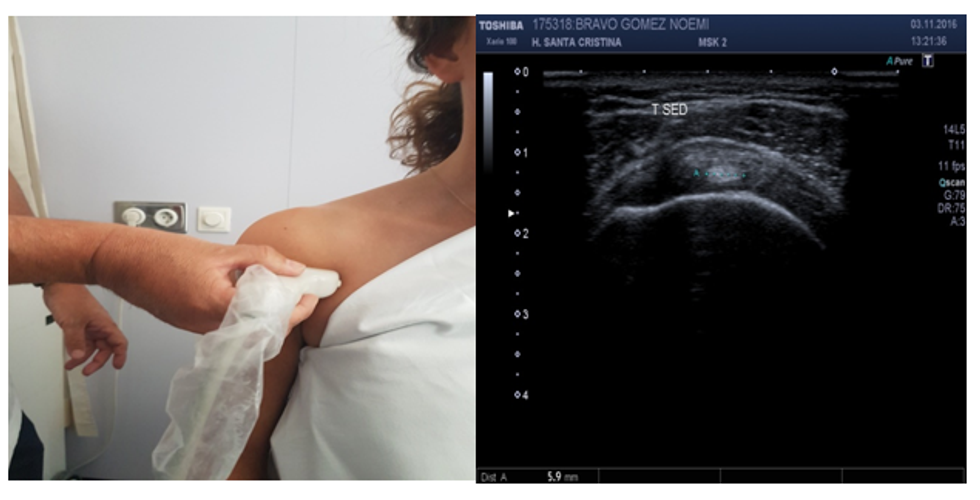

• Ekografitë përdorin valë zanore me frekuencë të lartë për të marrë një imazh të pjesës së brendshme të trupit. Ato mund të ndihmojnë mjekun tuaj të zbulojë problemet me nyjet, ligamentet dhe tendinat.